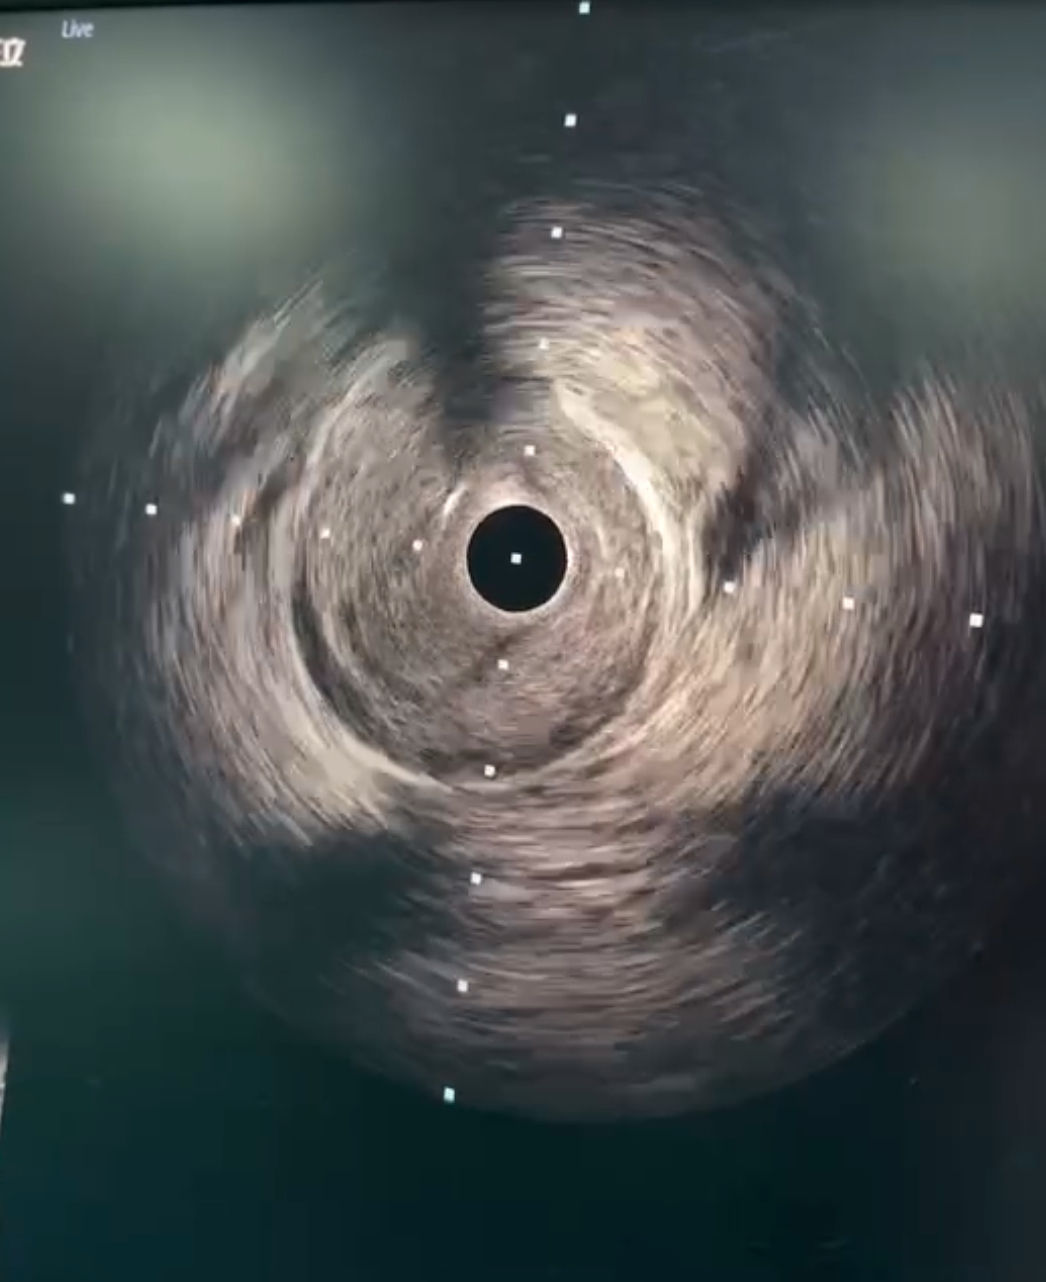

冠状动脉血管内超声

此刻,在县卫生局领导以及伍光晗院长指导下,现场的李小刚医师立刻参与冠状动脉血管内超声检查,同时积极与线上省内专家实时反馈与交流,最终为患者实施冠脉切割球囊治疗,治疗后,患者闭塞血管解除,转危为安。考虑患者为年轻女性的自发性夹层,未植入支架,后续采用药物治疗。此次远程联合诊治,使患者在短时间内化险为夷,赢得了线上及现场领导以及患者家属的一致好评,最终为患者带来了生存的希望。